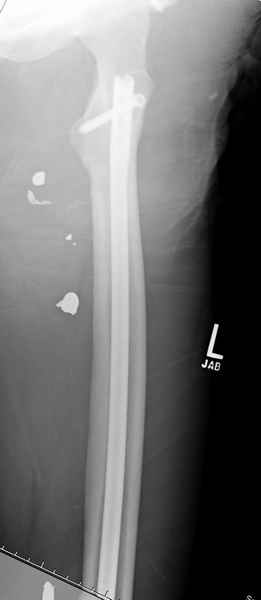

Входные маленькие отверстия от ранении просто игнорируются, никаких дренажей, как любое колотое ранения, они закрываются и были случаи через месяц. Конечно, ведется профилактика открытых ранении: сыворотки и т.д., но еще самое главное уделяем профилактике образования перелома из-за стресса в результате дефекта кортикального слоя.

Литературные данные о влиянии кортикального дефекта на стрессовые переломы в длинных трубчатых костях в основном встречаются в онкологии, например кортикальный дефект более 50% имеет больше шанса стрессовых переломов, чем в нашем случае.

Учитывая, что больной получил травму не во время визита в церковь, и он является одним из представителем 40 миллионного “outstanding itizen”, без медицинской страховки, без работы в свои 39 лет, и без надлежающей ортопедической дисциплины у которого отсутсвует страх стрессового перелома, было рекомендовано оперативное лечение: профилактическое антеградное интрамедуллярное штифтование.

Методика штифтования при отсутствии большой зоны перелома как при онкологических профилактических штифтованиях, расверливание интрамедуллярного канала проводим с предварительным наложением дополнительного дренажного отверстия в дистальном отделе бедра (в данном случаи в канале оставили 6.5 мм канюлированный шуруп), иначе при создании давления в канале во время сверления имеется опасность эмболизации легочной артерии тромбом.